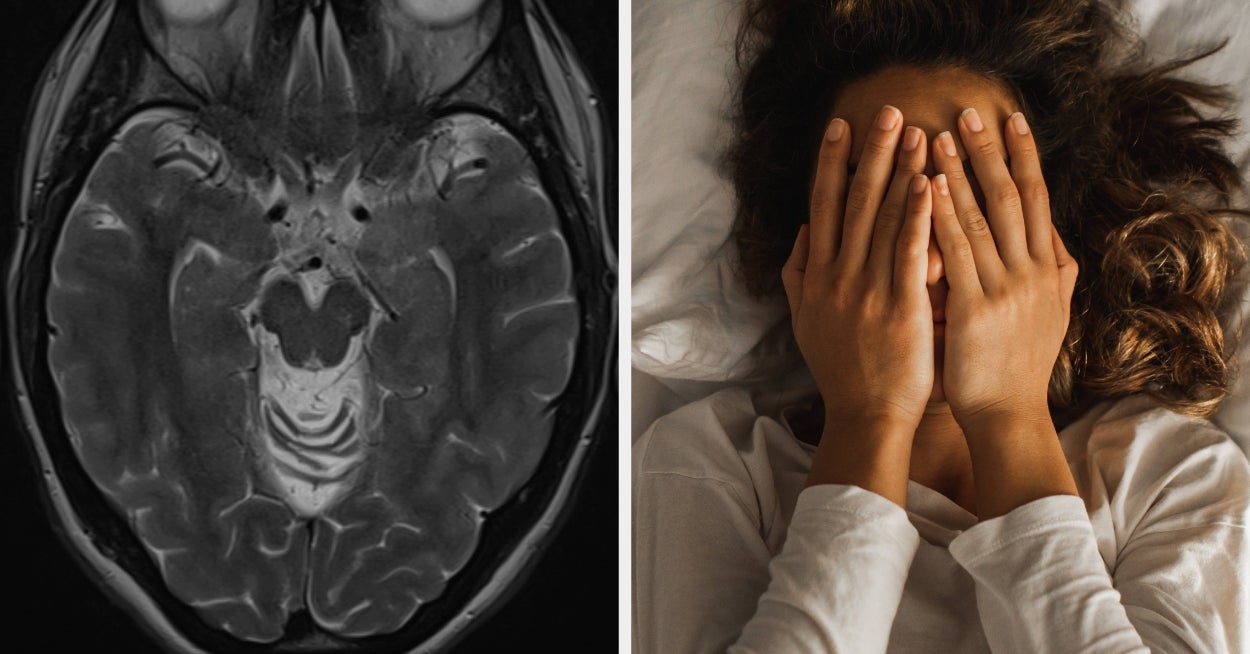

Neurologists Are Opening Up About Sleep Problems That Might Be Warning Signs Of Dementia

Experts reveal which sleep disturbances may signal something deeper, and when you should be concerned. This article originally appeared on HuffPost.